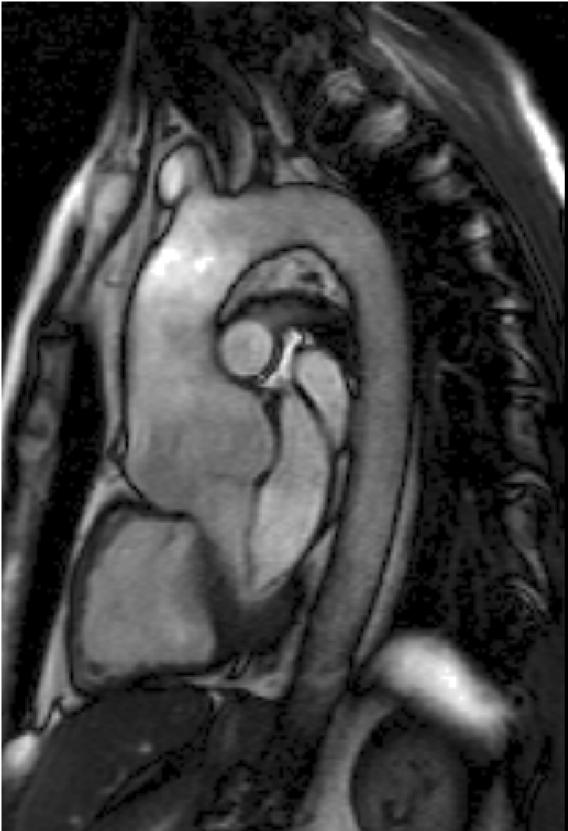

Double Trouble: Bicuspid Aortic Valve (BAV)

Let’s discuss what is a bicuspid aortic valve. The main valve of the heart - the aortic valve - is an incredibly beautiful structure with a level of design complexity that even the brilliant Renaissance artist and scientist, Leonardo da Vinci, marveled at.

All medical students and physicians have studied heart anatomy and know about the aortic valve.

However, for specialists like myself, there is a level of fasciation and depth of understanding... Continue reading.